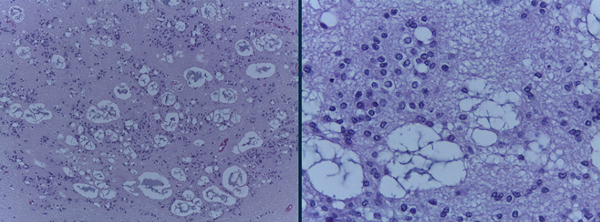

Se realizó la exéresis macroscópicamente completa de la lesión a través de una craneotomía y ulterior corticotomía a nivel del giro frontal medio derecho, colocándose finalmente una derivación ventricular externa (Figura 2). La anatomía patológica reveló una histología compatible con subependimoma grado I de la OMS (Figura 3). El paciente permaneció internado por 3 días en la unidad de terapia intensiva, pasando luego a piso donde se retiró la derivación ventricular externa y fue dado de alta hospitalaria al 5to día post operatorio sin complicaciones. Se realizó una RM control la cual evidenció la resección macroscópicamente completa de la lesión (Figura 4).

Figura 3: Anatomía patológica que evidencia histología compatible con Subependinoma Grado I de la WHO: Tumor con fondo de matric fibrilar glial. Células redondeadas con escaso pleomorfismo nuclear, formaciones micro quísticas y aisladas calcificaciones. El índice de proliferación celular expresado con K67 fue mejor que el 1%.